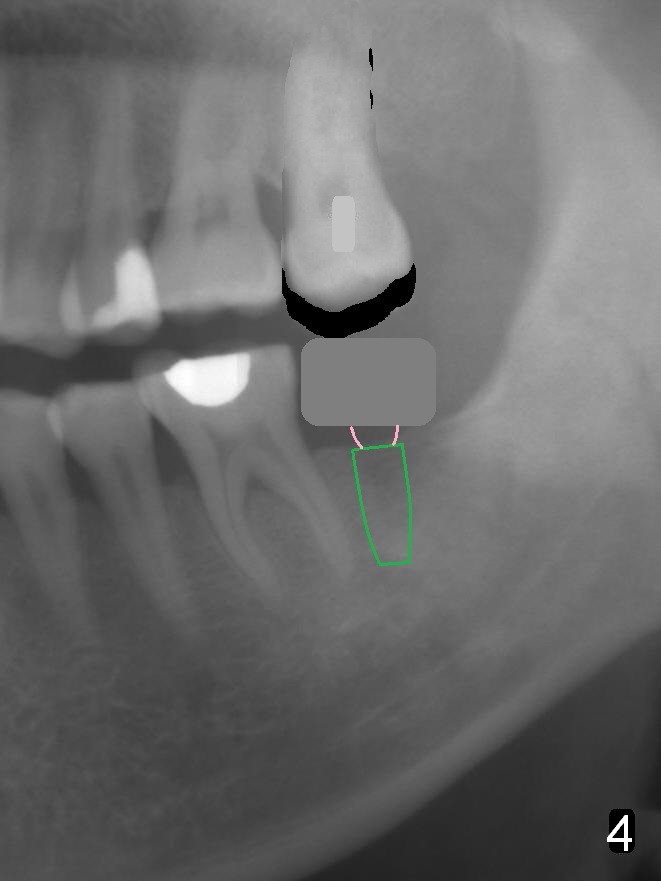

In fact, the tooth 15 had basically no extrusion 6 years earlier (Fig.2) with even occlusal plane. When the tooth is intruded orthodontically, the occlusal plane may be not even (Fig.3). When the implant at #18 osteointegrates (Fig.4 green), fabricate a provisional (grey rectangle) with higher mesial occlusal surface. For certain period of time, the tooth #15 may change its axis so that the mesial portion of the tooth may be intruded more (Fig.5 arrow).